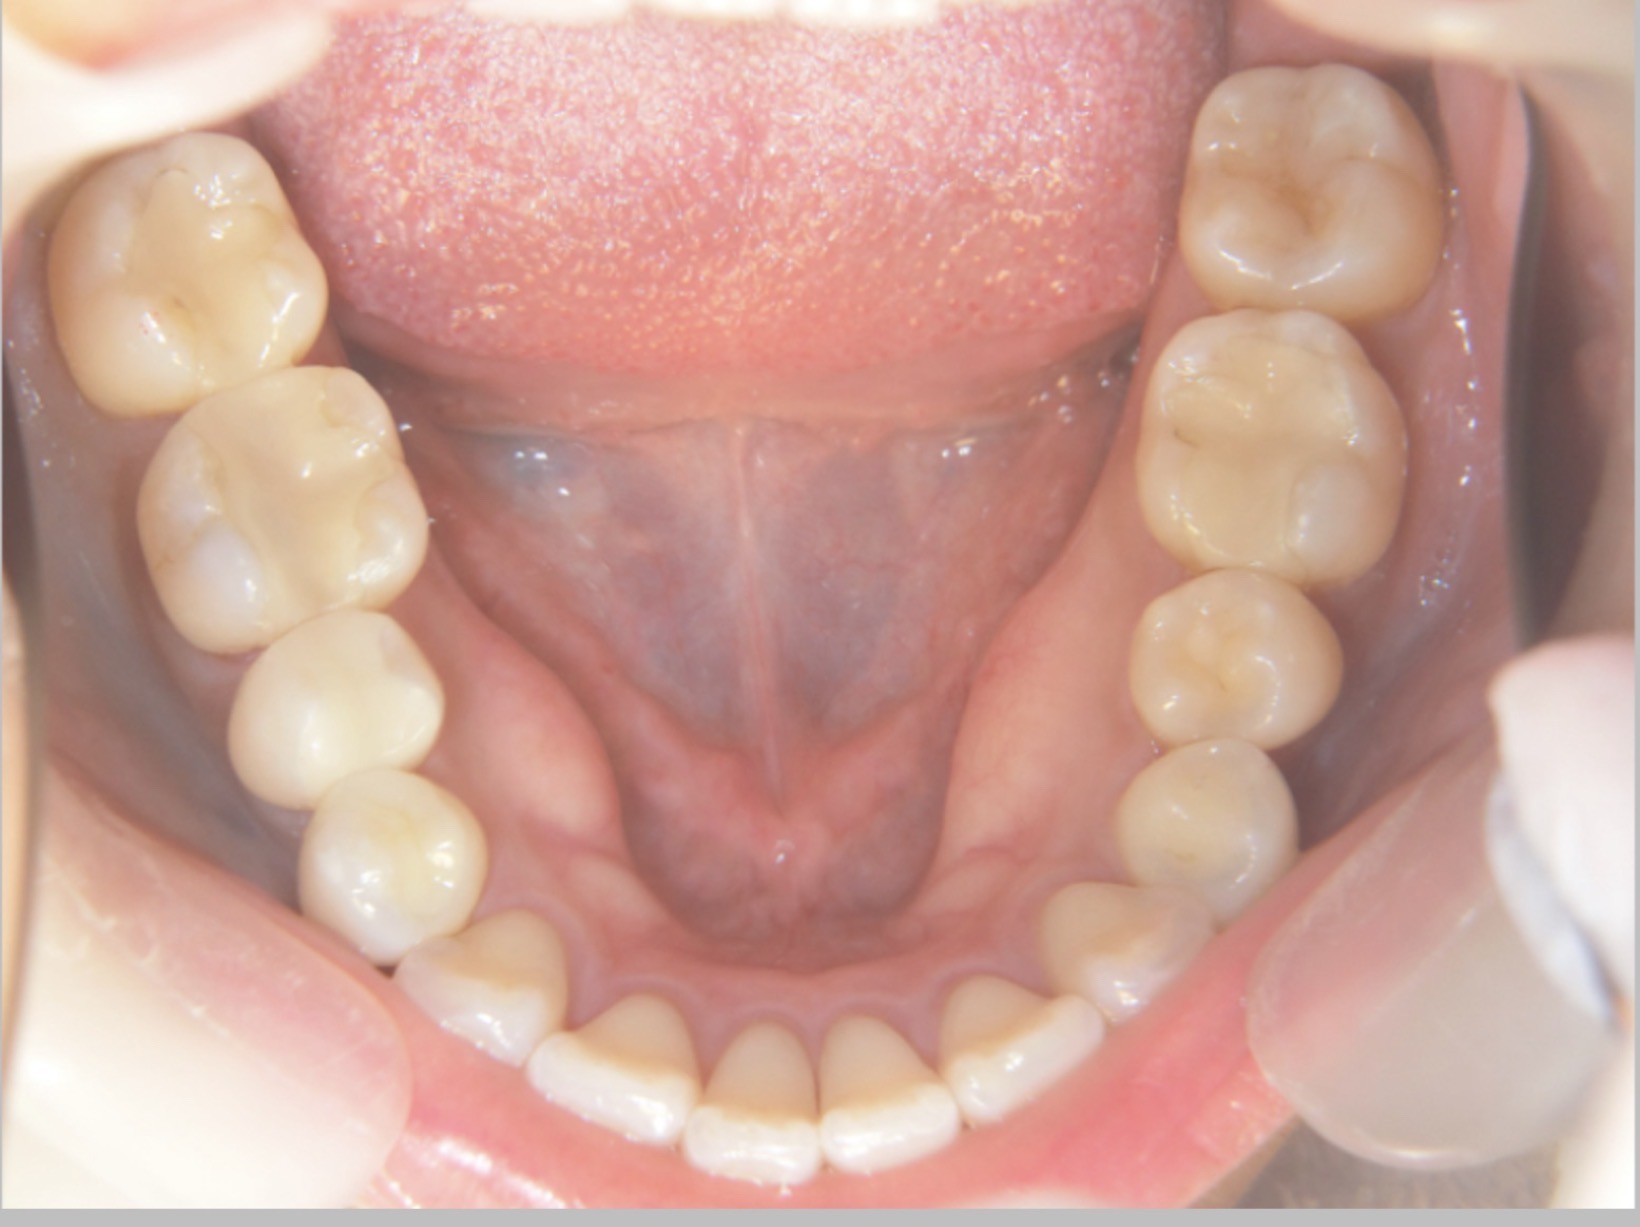

睡眠中の歯ぎしりや食いしばりは自覚しにくいことが特徴です。長期間にわたり口腔内に力が加わることで、顎の骨がその負荷に適応し、「骨隆起(こつりゅうき)」と呼ばれる骨のふくらみが形成されることがあります。

骨隆起は下顎の内側(舌の付け根付近)や上顎中央部に見られ、自覚症状がないまま進行するケースも少なくありません。

舌で触れた際に「内側に硬い出っ張りがある」と感じる方は、一度確認のきっかけになる場合があります。「自分には関係ない」と思っている方でも、実際に確認すると見られるケースは少なくありません。

当院の臨床では、20代後半の患者においても骨隆起が確認される例があり、無意識の咬合圧が比較的若い年代から蓄積している可能性も考えられます。